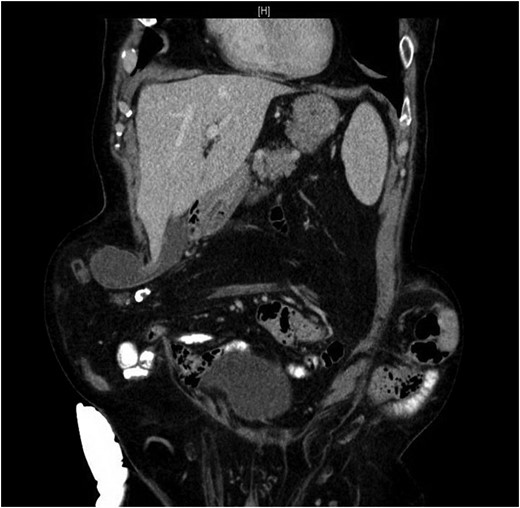

Our patient is an 89-year-old male with a history of a Hartmann’s procedure (2006) for Crohn’s disease of the sigmoid colon followed by a reversal of the colostomy with a diverting loop ileostomy (2008). Due to his comorbidities and age, the patient declined further surgery to reverse his loop ileostomy. Most recently, the patient presented to the emergency room with no ostomy output for the past 14 h, nausea and frequent burping. He reported a burning sensation around his ostomy. His physical examination revealed a large parastomal hernia in the right hemiabdomen and associated tenderness in the right upper quadrant, with no overlying skin changes. His white blood cell count was 8.1 (82.4% neutrophils), and he had normal liver function tests. A computed tomography (CT) scan of the abdomen and pelvis revealed a large parastomal hernia with a wide neck containing a distended gallbladder concerning for acute cholecystitis, as well as a small bowel obstruction with a transition point at the level of the hernia (Figs 1 and 2). A previous CT scan showed the same hernia with a nondistended gallbladder and non-obstructed bowel entering and exiting the stoma (Fig. 3).

CT from current admission with distended gallbladder consistent with acute cholecystitis.